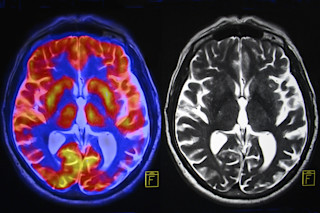

所有成瘾性药物都在大脑内起作用,但它们产生的欣快感往往是有代价的。有些药物会导致大脑损伤,引发癫痫或中风,甚至直接对脑细胞产生毒性作用。

例如,可卡因会导致大脑出现微小中风,在大脑的神经回路中形成坏死点。并且,毒瘾在一定程度上被定义为它能够引起大脑的长期变化。这些变化会影响大脑的不同回路,包括那些控制快乐、压力、冲动控制、学习和记忆的回路。

多年来,研究人员一直致力于对抗这些变化,利用大脑的适应和修复能力。由于大脑具有“可塑性”,或者说能够适应和改变,它可以利用其他神经回路来执行被受损细胞禁用的功能。